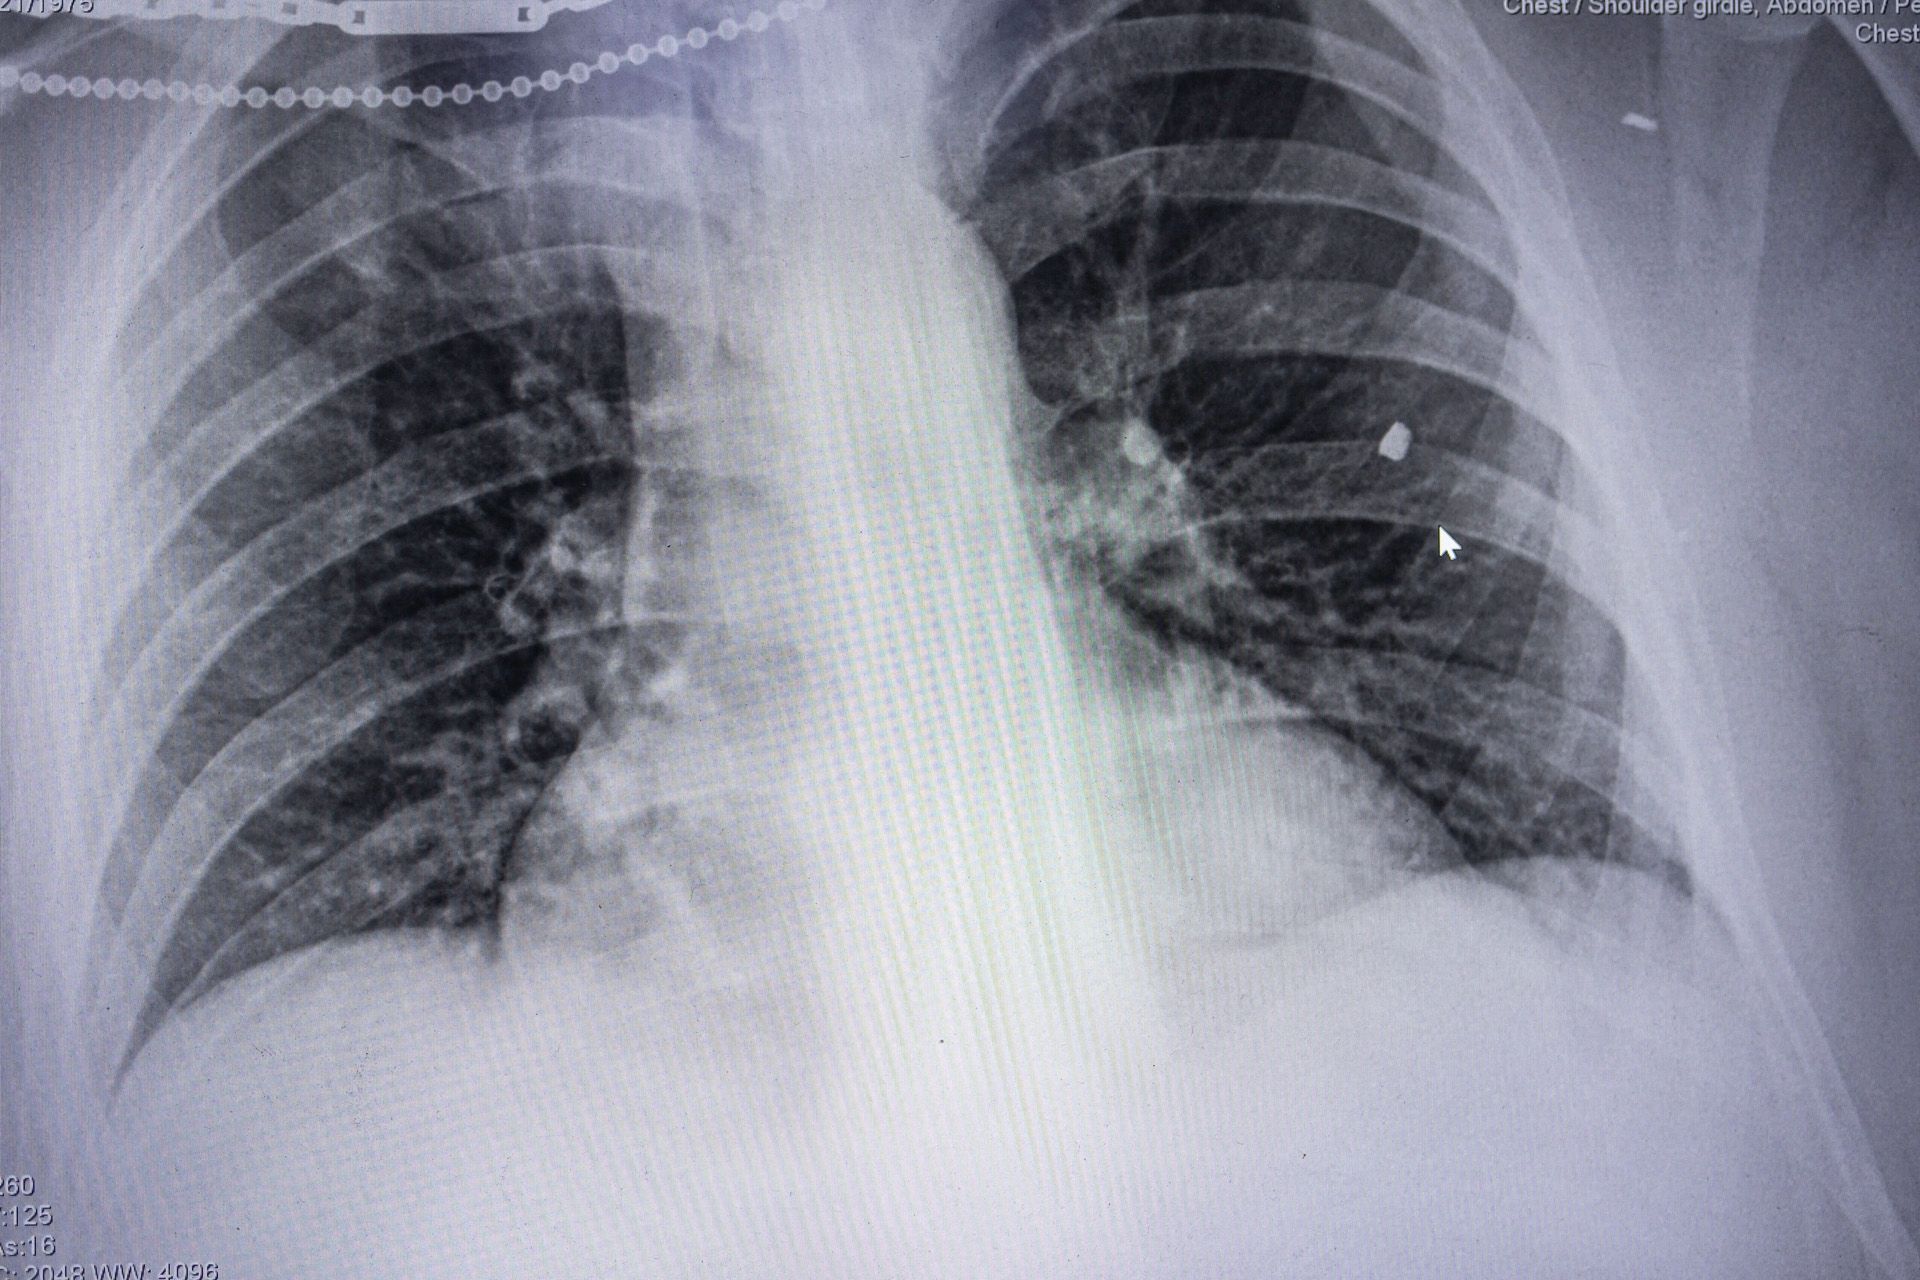

Diego Herrera Carcedo / Anadolu / ABACAPRESS / ddp images / Vida Press Шрапнель на рентгеновском снимке раненого украинского военного, 16 августа 2024 года